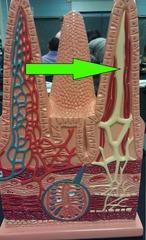

arrow

small intestine model

green

Villus (s.) Villi (pl.)

Microvillus (s.) Microvilli (pl.)

Lacteal

Goblet cells